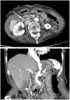

Carcinoma of ampulla

The ampulla of Vater, also known as the hepatopancreatic ampulla or the hepatopancreatic duct, is formed by the union of the pancreatic duct and the common bile duct. The ampulla is specifically located at the major duodenal papilla. [Source: Wikipedia ]